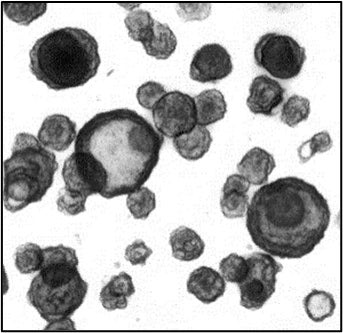

単層培養した小腸オルガノイドにシスプラチンを5日間処理することで、細胞老化の検出方法であるSA β-gal染色により染色される細胞の数が増加したことを確認しました(図1)。また、遺伝子発現量を評価したところ、シスプラチンの処理により細胞老化や炎症に関する遺伝子の発現量が増加したことを確認しました(図2)。

ヒトiPS細胞由来小腸オルガノイドを用いて、老化の特徴である細胞の老化と、それに伴う炎症反応、バリア機能の低下などを再現したモデルの構築に成功しました。(図1)